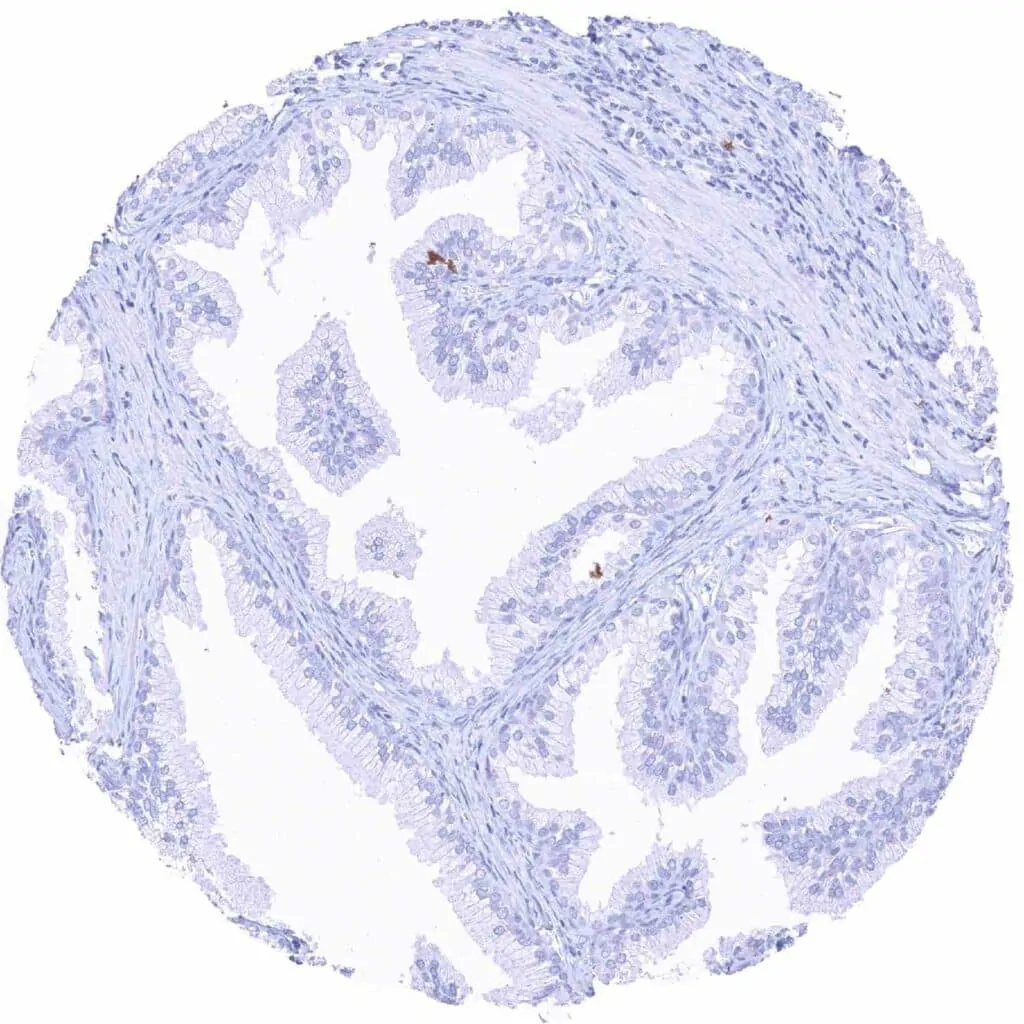

Uterus, endocervix